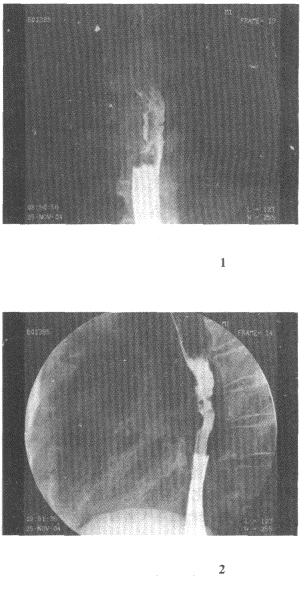

2.男,74歲,進(jìn)行性吞咽困難半年,結(jié)合圖像,最可能的診斷為

正確答案:D 解題思路:食管中段鋇劑通過(guò)見(jiàn)半圓形充盈缺損,病灶附近黏膜粗細(xì)不均、扭曲,結(jié)合患者病史,考慮食管中段癌性病變。